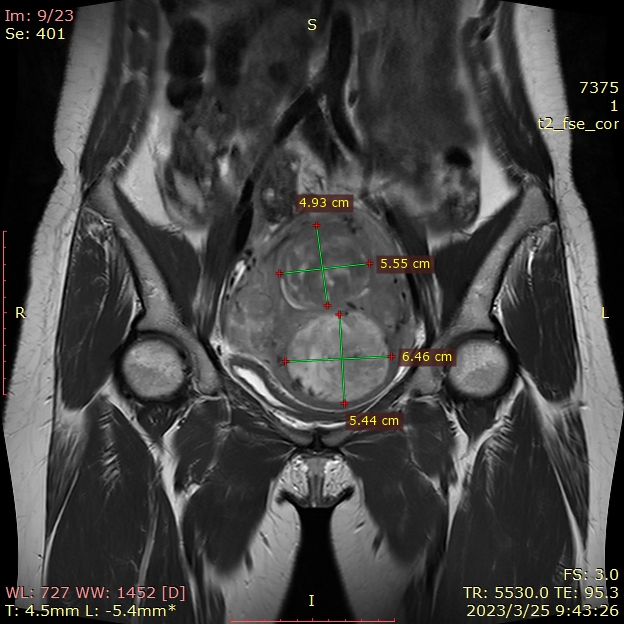

✦超声和MRI提示子宫多发肌瘤,较大者4-5型,T2高信号,71mm*58mm*67mm,次之2型,大小51mm*36mm*55mm,体检提示子宫如孕10周大小。

✦术前肌瘤大小:前壁4-5型肌瘤59mm*52mm,2型肌瘤43mm*40mm。